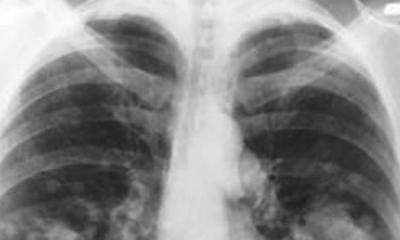

Lung cancer rates rising in the United States

ILLINOIS (WAND) – Statistics show Illinois has work to do when it comes to treating lung cancer.